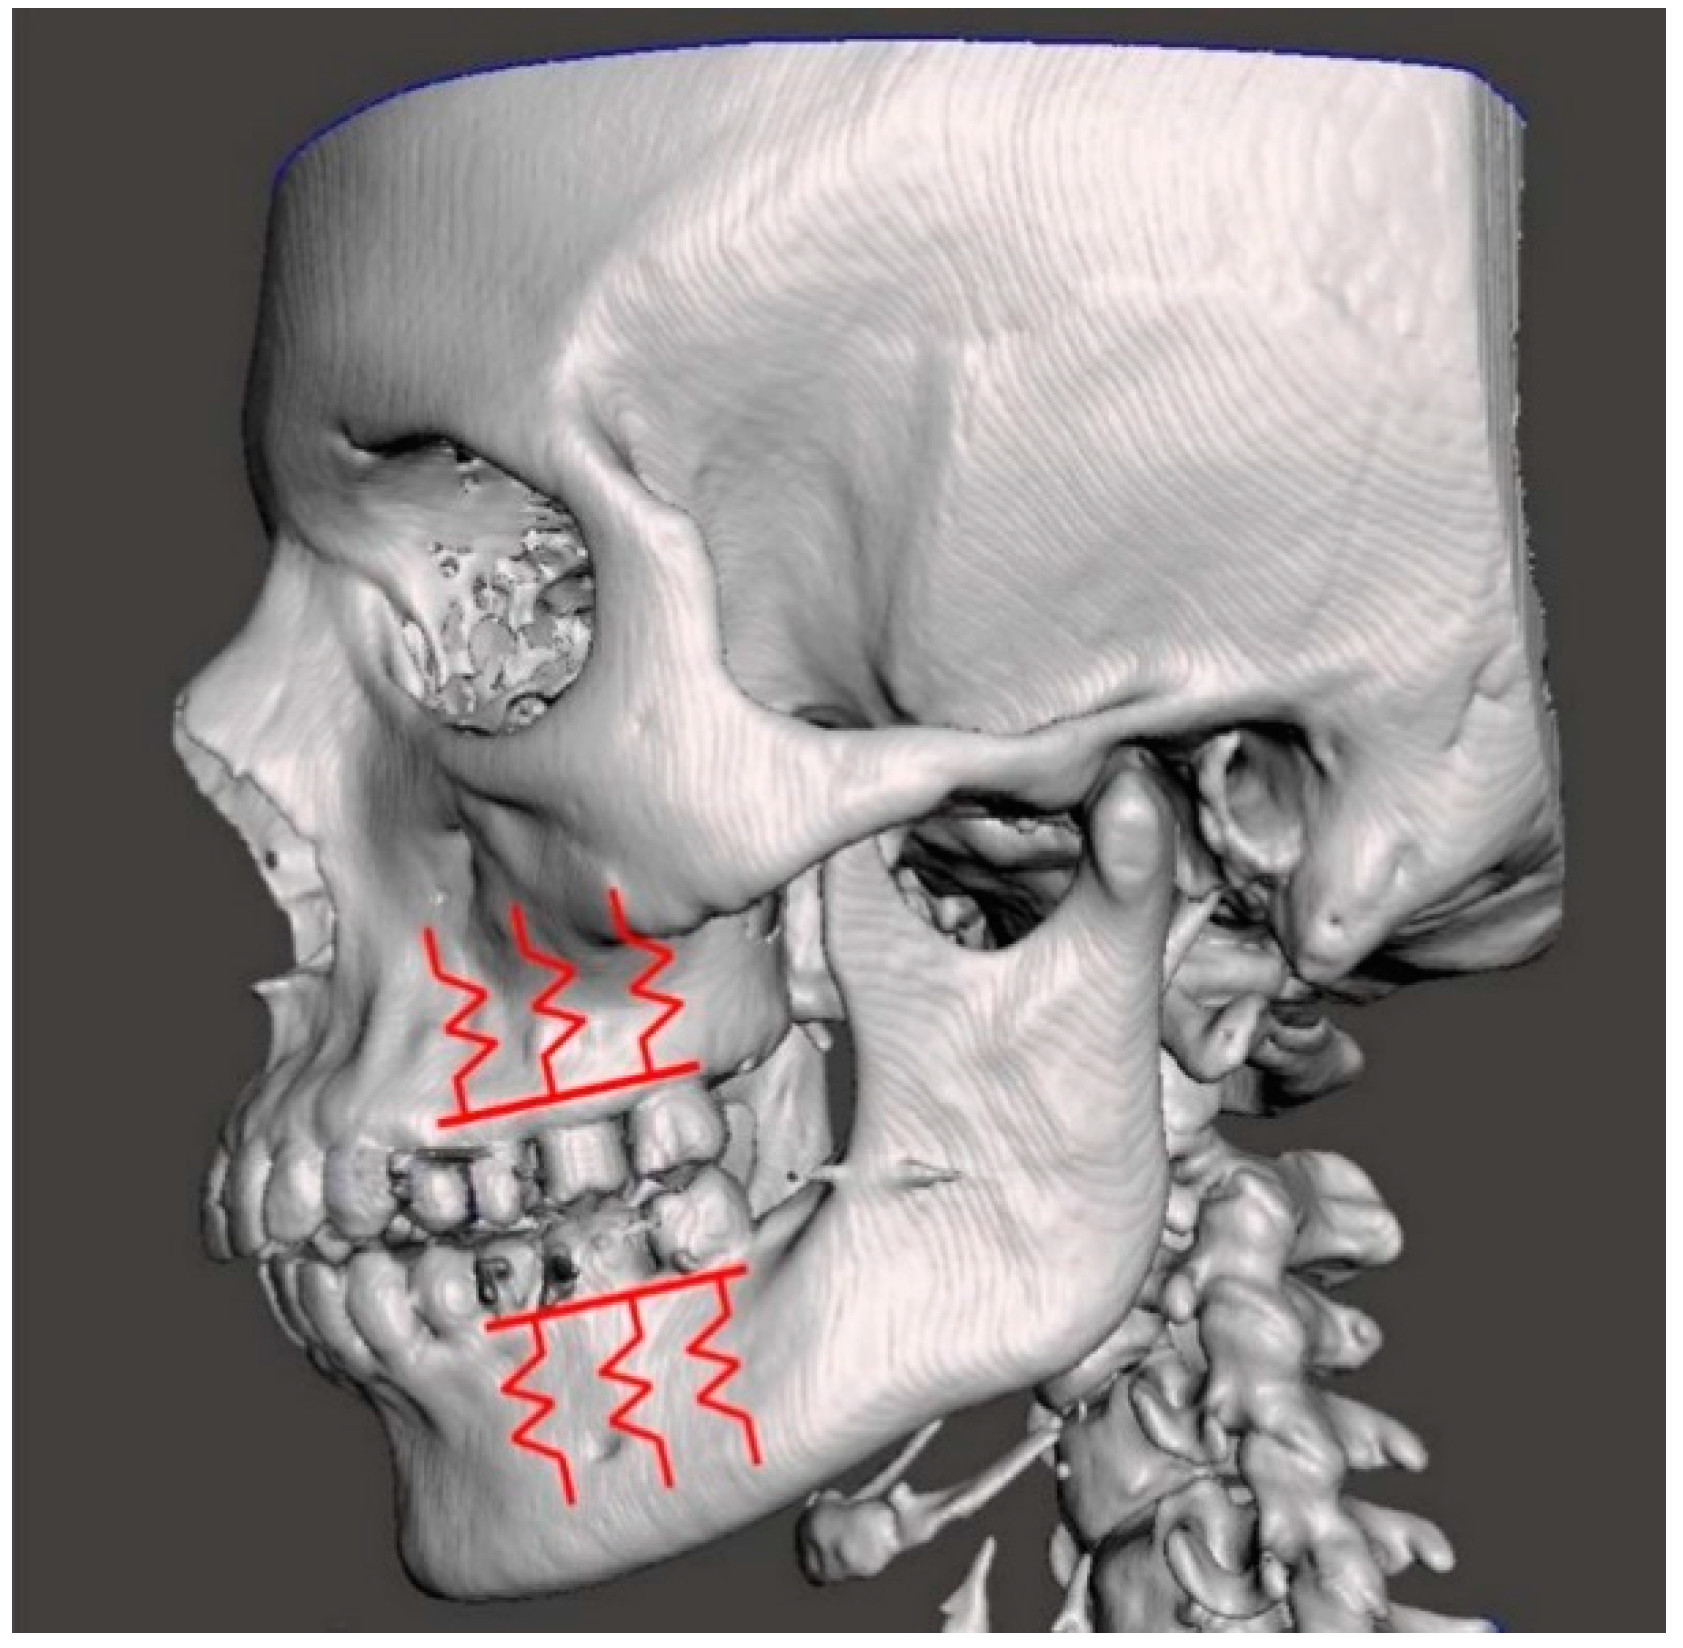

2.2. Case Study of a Maxillary Exostosis: Congruence and Contact Evaluation